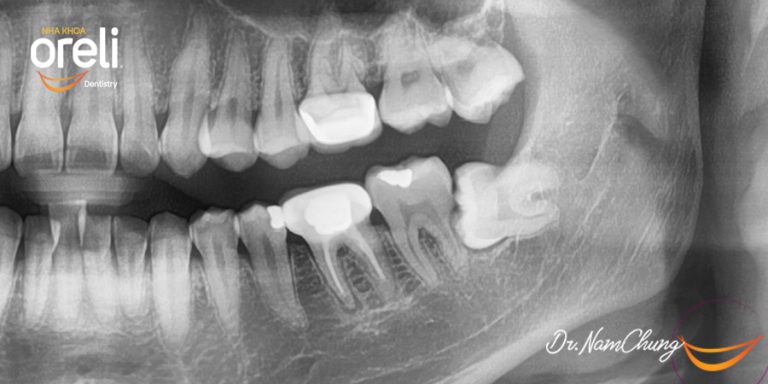

Nhổ răng khôn hàm dưới – Case tại Oreli Buôn Ma Thuột

Nhổ răng khôn

Mọc lệch

Xem thêm